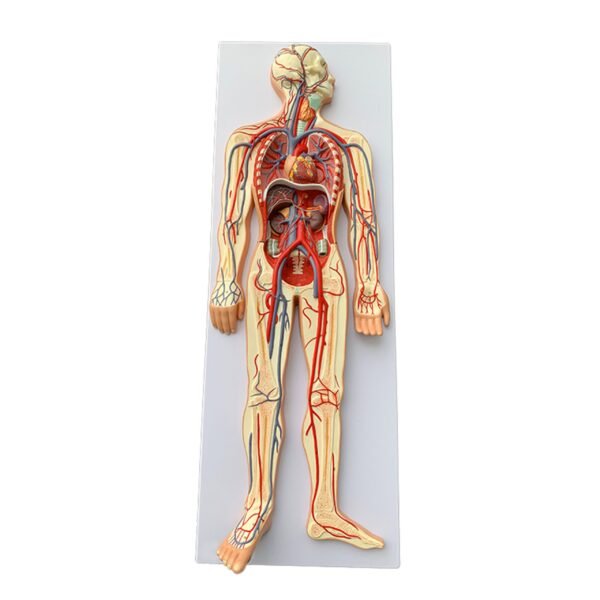

Blood Circulatory System model

* Size: 1/2 of natural size, height 86cm, width 30cm, thickness 5cm.

* Material: PVC material, imported paint, computer color matching, high-level painting

* The model shows the main arteries and veins of the systemic blood circulation, with a total of 81 indications.

* This model is a premium, medical quality anatomical model made in non-toxic PVC material design to be easily cleanable and withstand high temperatures.